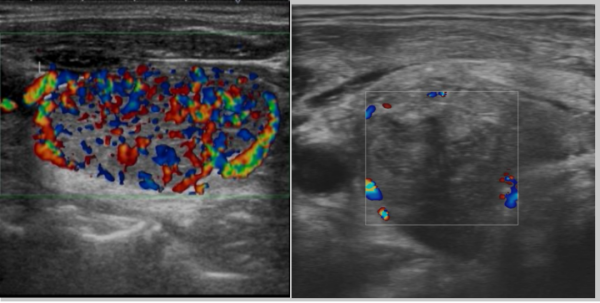

入院第一天穿刺活检明确右侧甲状腺结节为良性腺瘤,因患者担心放射性碘治疗引起腺瘤恶变,排除相关禁忌证后,入院第二天,针对弥漫性甲状腺肿伴甲状腺功能亢进张女士接受了微波热消融治疗,整个消融时间仅花费10分钟,入院第三天复查超声血流图可以看出消融前甲状腺腺体内的“火海征”消失,证明消融十分成功,当天康复出院。

微波消融治疗前的甲状腺(火海征) 微波消融治疗后的甲状腺